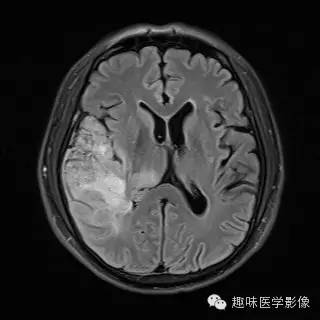

【病例】少突胶质细胞瘤1例MR影像表现

性别:男年龄:48岁 间断性四肢抽搐9月余,头晕伴肢体无力1月余

[影像表现]

右侧颞顶叶、丘脑可见大片不规则异常信号灶,局部脑回肿胀,大小约45×75mm,T1WI呈混杂低信号,内可见多发条状高信号,中央可见更低信号灶,T2WI/FLAIR呈混杂稍高信号,内可见点状低信号,DWI呈混杂高信号,未见明显占位效应,增强后呈多发不规则花环状明显强化灶,内可见多发点状小血管影。

少突胶质细胞瘤,WHOⅡ级。

少突胶质细胞瘤为分化良好、生长缓慢但呈浸润性的肿瘤,典型者累及皮层和皮层下白质,20%-50%有侵袭性(间变性少突胶质瘤)。最佳诊断征象:部分钙化 中年人的皮层肿块,可以侵蚀并使颅骨膨胀。CT平扫为低/等密度,大部分钙化,可有出血和囊变,增强CT表现多样,从无增强到明显增强。MRI常不均匀,T1WI上相对于皮层为低/等信号,T2WI为高信号;除间变外,出血、坏死少见,边界清楚,伴轻微水肿,50%强化。